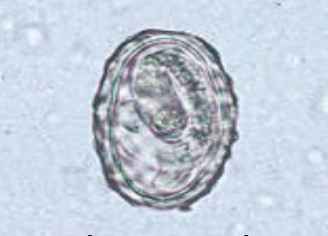

Enterobius vermicularis egg morphology

colorless and smooth

thick shell flattened on one side

elongate-oval

can contain fully developed larvae

what species produces this egg?

Enterobius vermicularis